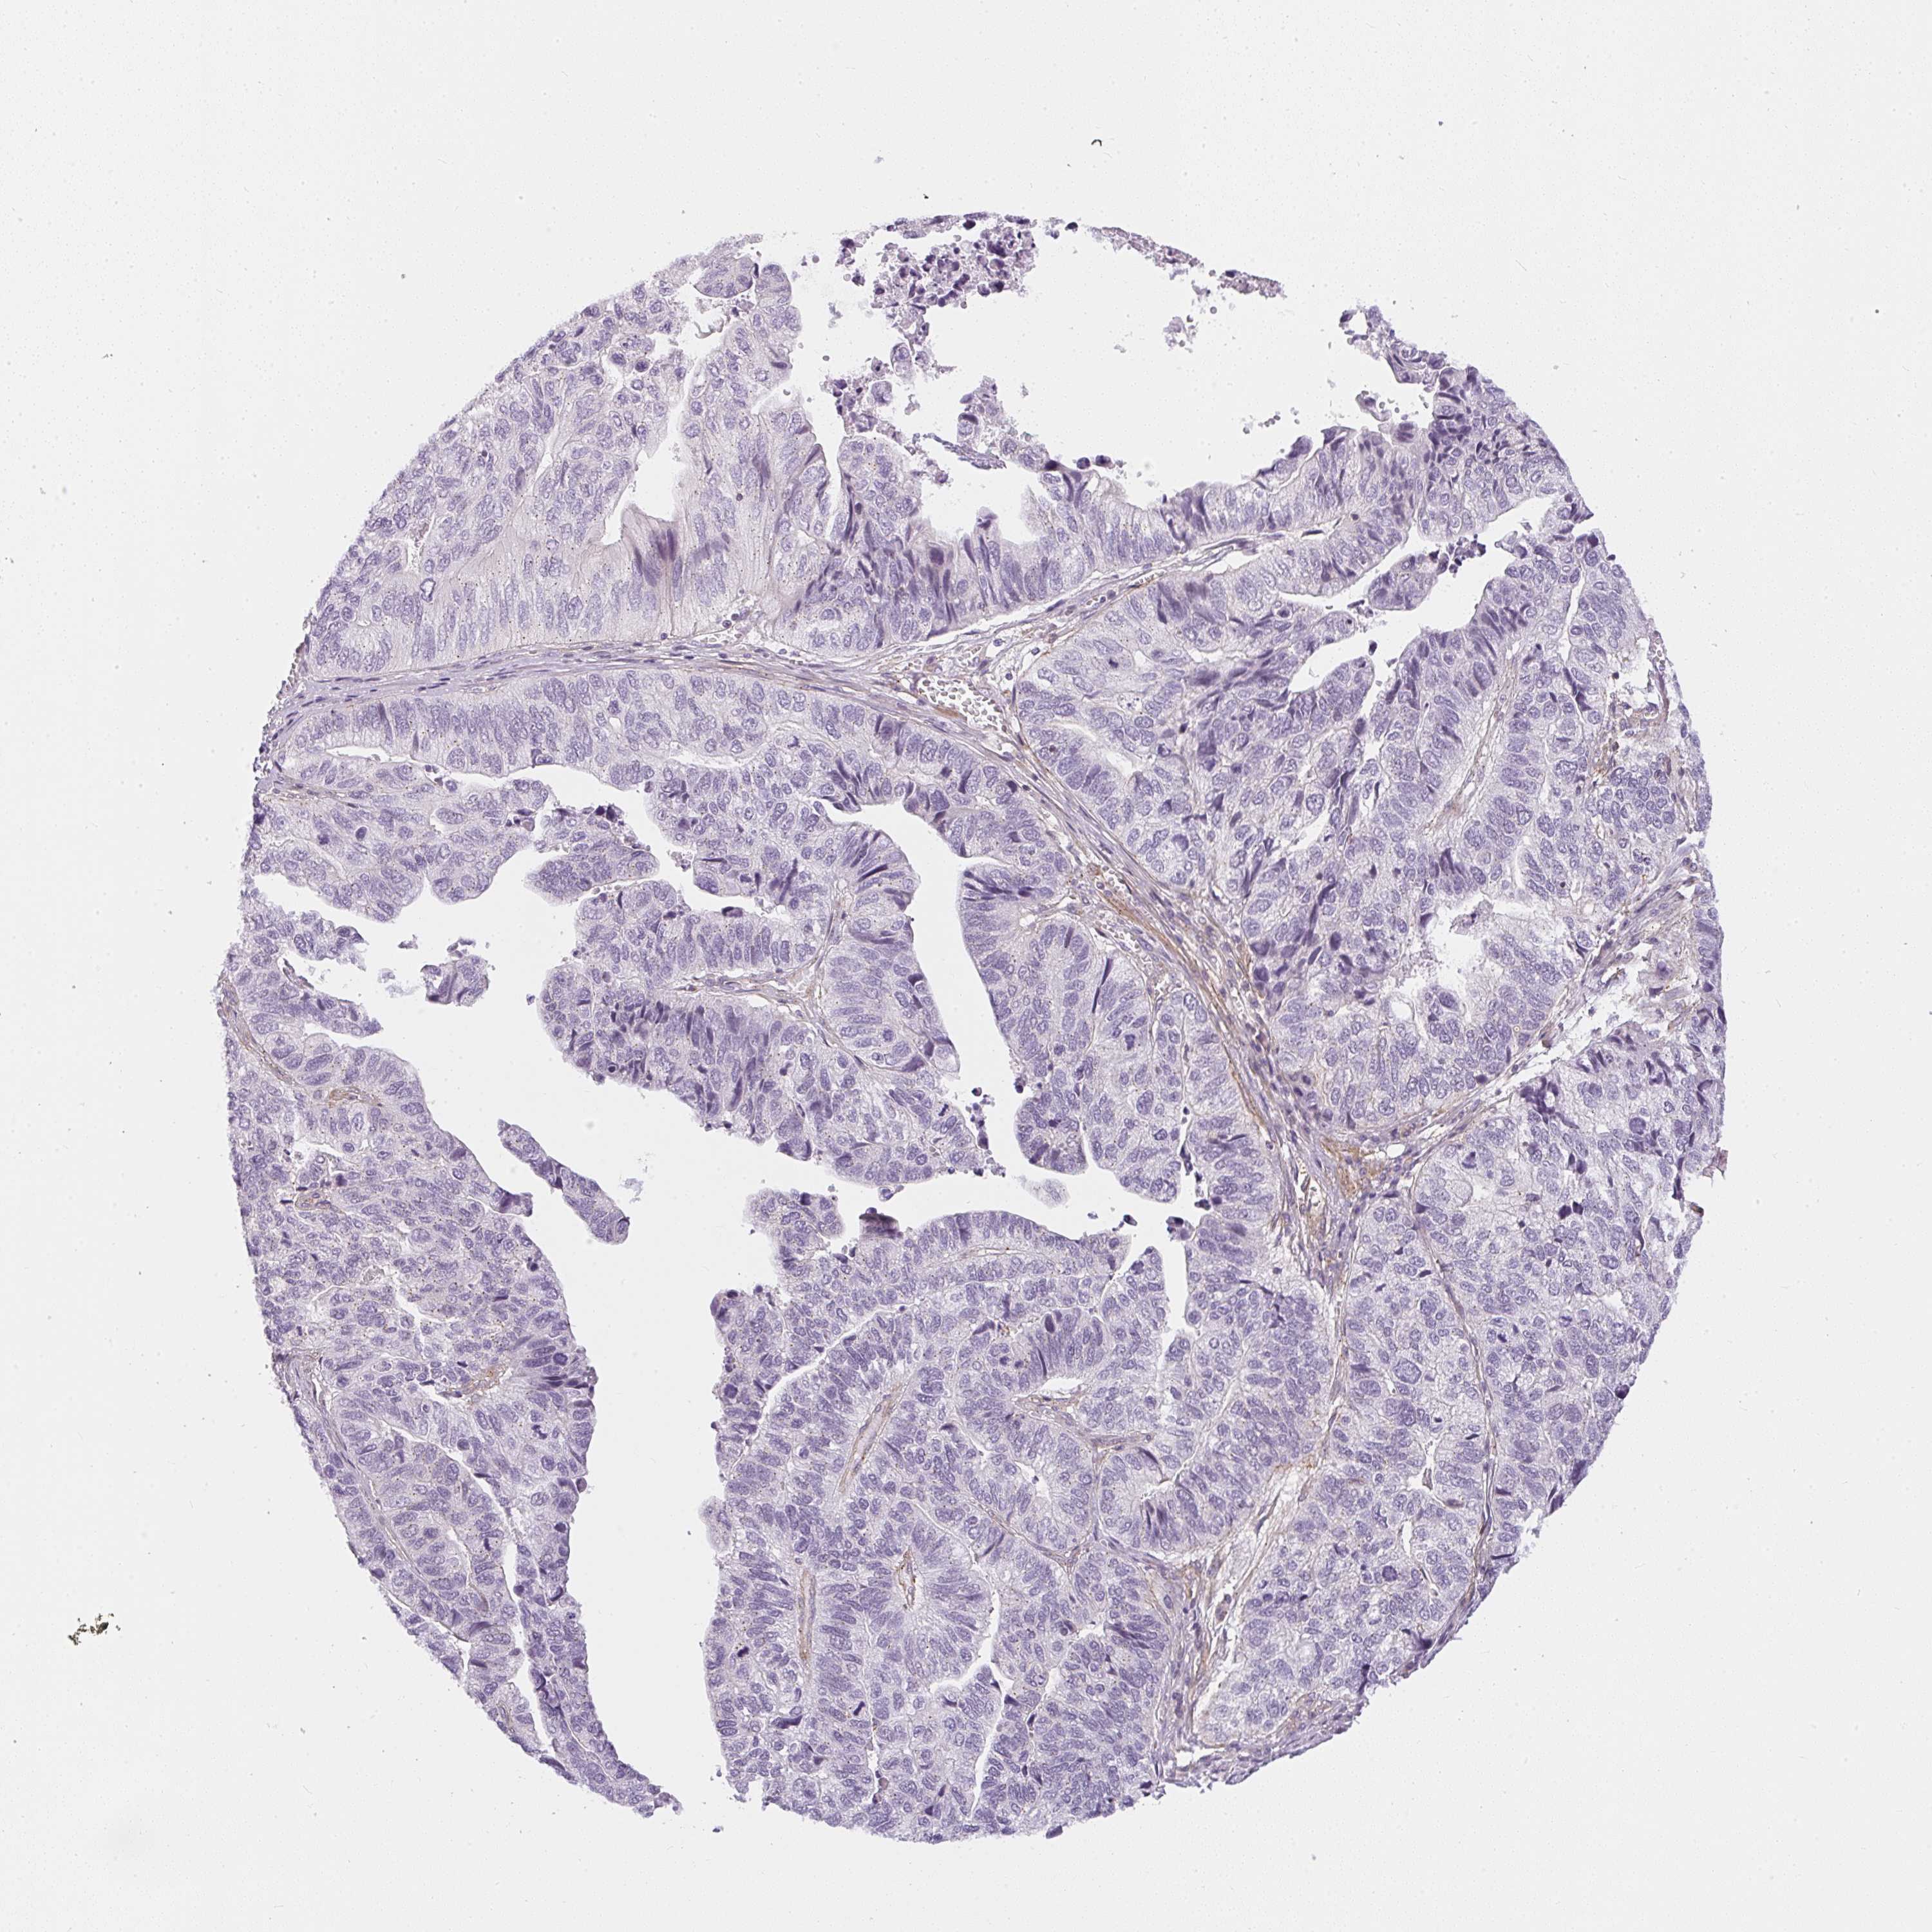

STOMACH CANCER - Protein expressioni

A mouse-over function shows sample information and annotation data. Click on an image to view it in a full screen mode. Samples can be filtered based on level of antibody staining by selecting one or several of the following categories: high, medium, low and not detected. The assay and annotation is described here.

Antibody stainingi

Antibody staining in the annotated cell types in the current human tissue is reported as not detected, low, medium, or high, based on conventional immunohistochemistry profiling in selected tissues. This score is based on the combination of the staining intensity and fraction of stained cells.

Each image is clickable and will lead to virtual microscopy that enables deeper exploration of all samples and also displays staining intensity scores, fraction scores and subcellular localization as well as patient and tissue information for each sample.

Antibody HPA054728

Staining

High

Medium

Low

Not detected

Intensity

Strong

Moderate

Weak

Negative

Quantity

>75%

75%-25%

<25%

None

Location

Nuclear

Cytoplasmic/membranous

Cytoplasmic/membranous,nuclear

Adenocarcinoma, NOS